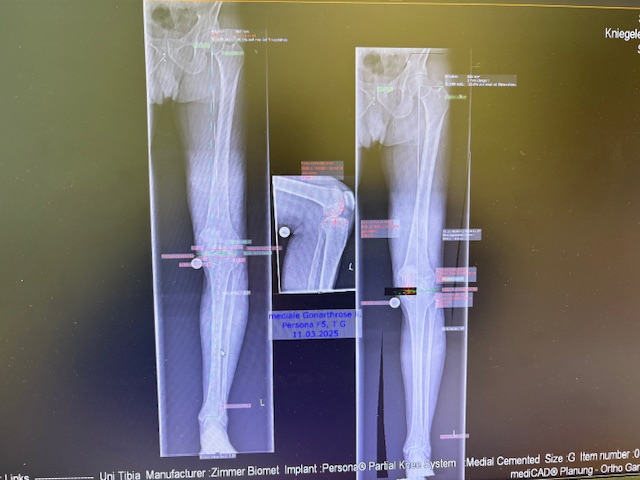

Ο προεγχειρητικός ψηφιακός σχεδιασμός

Πραγματοποιήθηκε απεικόνιση και ψηφιακός σχεδιασμός της επέμβασης, ώστε να προσδιοριστεί με ακρίβεια το μέγεθος και η θέση των προθέσεων. Ο στόχος ήταν να αποκατασταθεί η φυσιολογική μηχανική του γόνατος, διατηρώντας ανέπαφα τα υγιή τμήματα της άρθρωσης, τους συνδέσμους και τους γύρω μυς.

Στον ασθενή τα εμφυτεύματα που χρησιμοποιήθηκαν είναι της εταιρείας Zimmer-Biomet Persona Μηριαίο μέγεθος 6, κνημιαίο μέγεθος Η και ενθέμα (inlay) Η li. 8mm.